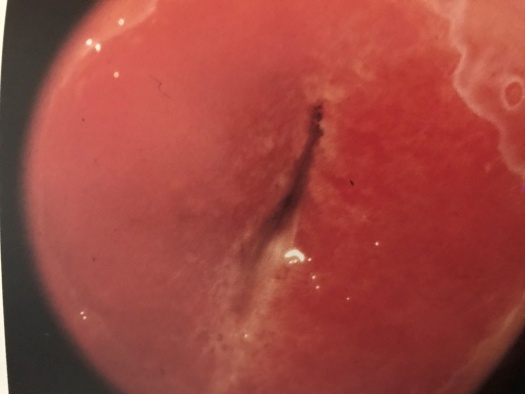

宫颈柱状上皮异位

宫颈表面的细胞在胚胎发育期大致分为两种,以宫颈外口为界,宫颈管内为柱状上皮细胞,宫颈管以外为鳞状上皮细胞。青春期后,在雌激素的作用下,柱状上皮细胞增生,向外爬行,暴露于宫颈管以外,这便是“柱状上皮异位”。由于柱状细胞下方具有丰富的血管网,致使宫颈呈现红色,又由于柱状上皮细胞相互融合,呈绒毛状或颗粒状突起,看起来红红的,糙糙的,貌似“糜烂”。绝经后,雌激素水平低落或缺乏,柱状上皮细胞回缩至宫颈管内,这一现象便不复存在。也不是所有的人,在所有的时期都会出现这种现象,主要取决于宫颈柱状上皮细胞对雌激素的反应性。一言以概之,“宫颈糜烂”是“柱状上皮异位”的表现,是正常生理现象,不是病!更与宫颈癌扯不上边。